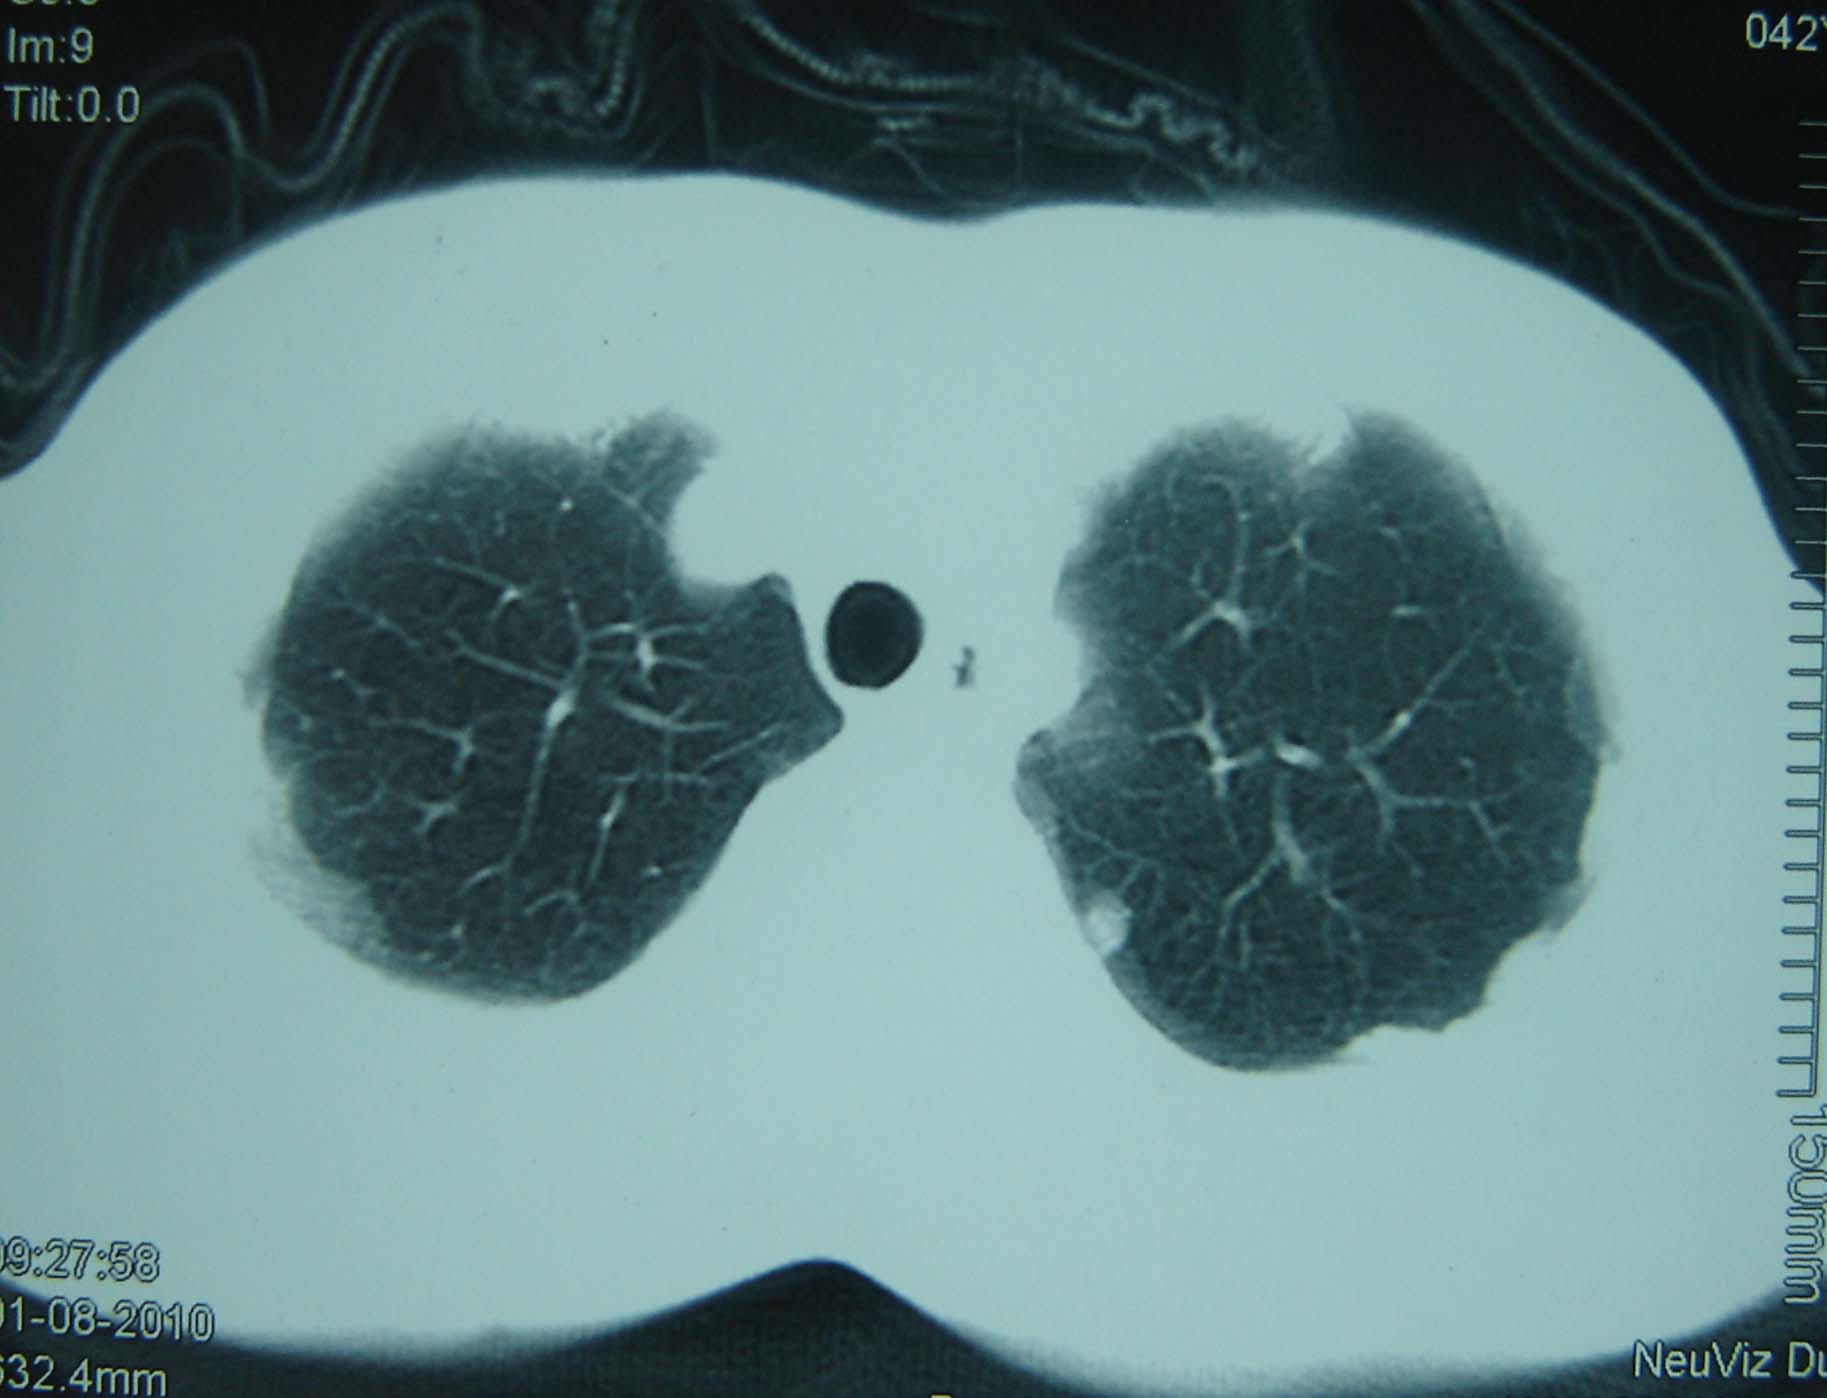

标题: CT25321:两肺多发结节 请会诊 [打印本页]

男 、43岁,咳嗽胸痛,装修工,平时接触粉尘较多,有吸烟史10多年,纤维支气管镜检查未发现异常,胃镜、腹部b超检查亦未发现异常,颈部淋巴结活检未发现肿瘤细胞。